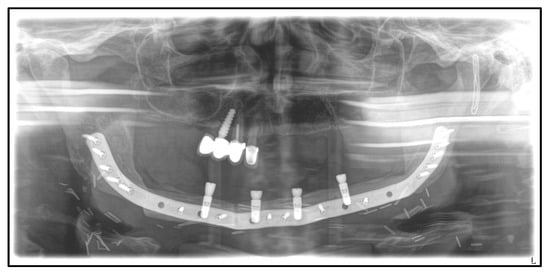

| Date | Intervention |

|---|---|

| 2016: | Diagnosis of breast cancer with osseous metastasis. Mammectomy, adjuvant radiation, and intravenous bisphosphonate therapy with zoledronate 4 mg every 6 months (2016–January 2019). |

| 2019: | Extraction of the lower left canine and first premolar due to intraoral pus leakage by the general dentist. |

| January 2020: | Admission to hospital with MRONJ of the left mandible and recurrent fistulation/pus leakage. |

| April 2020: | Partial mandibular resection from the left to the right mandibular angle, CAD/CAM-assisted reconstruction using a free fibular graft and PSI, temporary tracheostomy. In the course: development of aspiration pneumonia treated with piperacillin and tazobactam 4.5 g for 8 days. |

| April 2021: | Placement of four dental implants in the neo-mandible for dental rehabilitation. |

| August 2021: | Surgical removal of the upper right incisor, smoothening of the bone, primary wound closure, perioperative antibiosis with ampicillin and sulbactam |